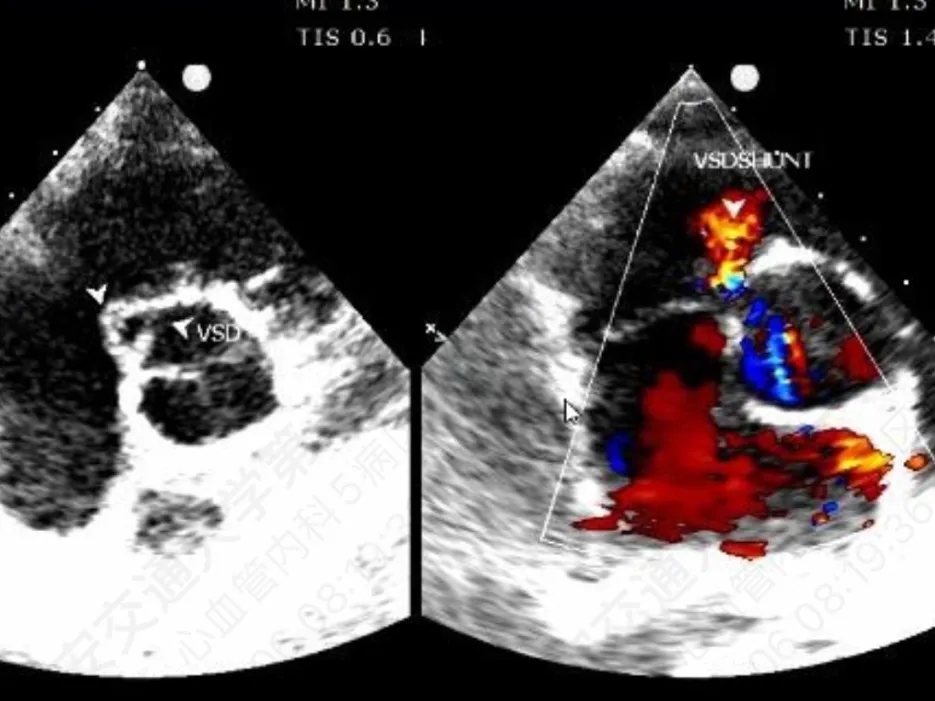

术前超声与DSA复测

VSD(膜周部):室间隔膜部瘤,左室面6.5mm,右室面呈“瘤样”结构,瘤体深度7mm,出口2mm。

该病灶呈现为“长隧道、大瘤底、小出口”的细腰形态,且位置紧邻主动脉瓣与三尖瓣,解剖结构较为复杂。此形态特征使得可降解封堵器在植入过程中的定位与释放面临较大挑战。

VSD(膜周部):左室面6.5mm,隔瓣下残缘5mm,基底形成5mm入口,右室面呈“瘤样”结构,出口孔2.5mm,三尖瓣隔瓣构成瘤壁的一部分。